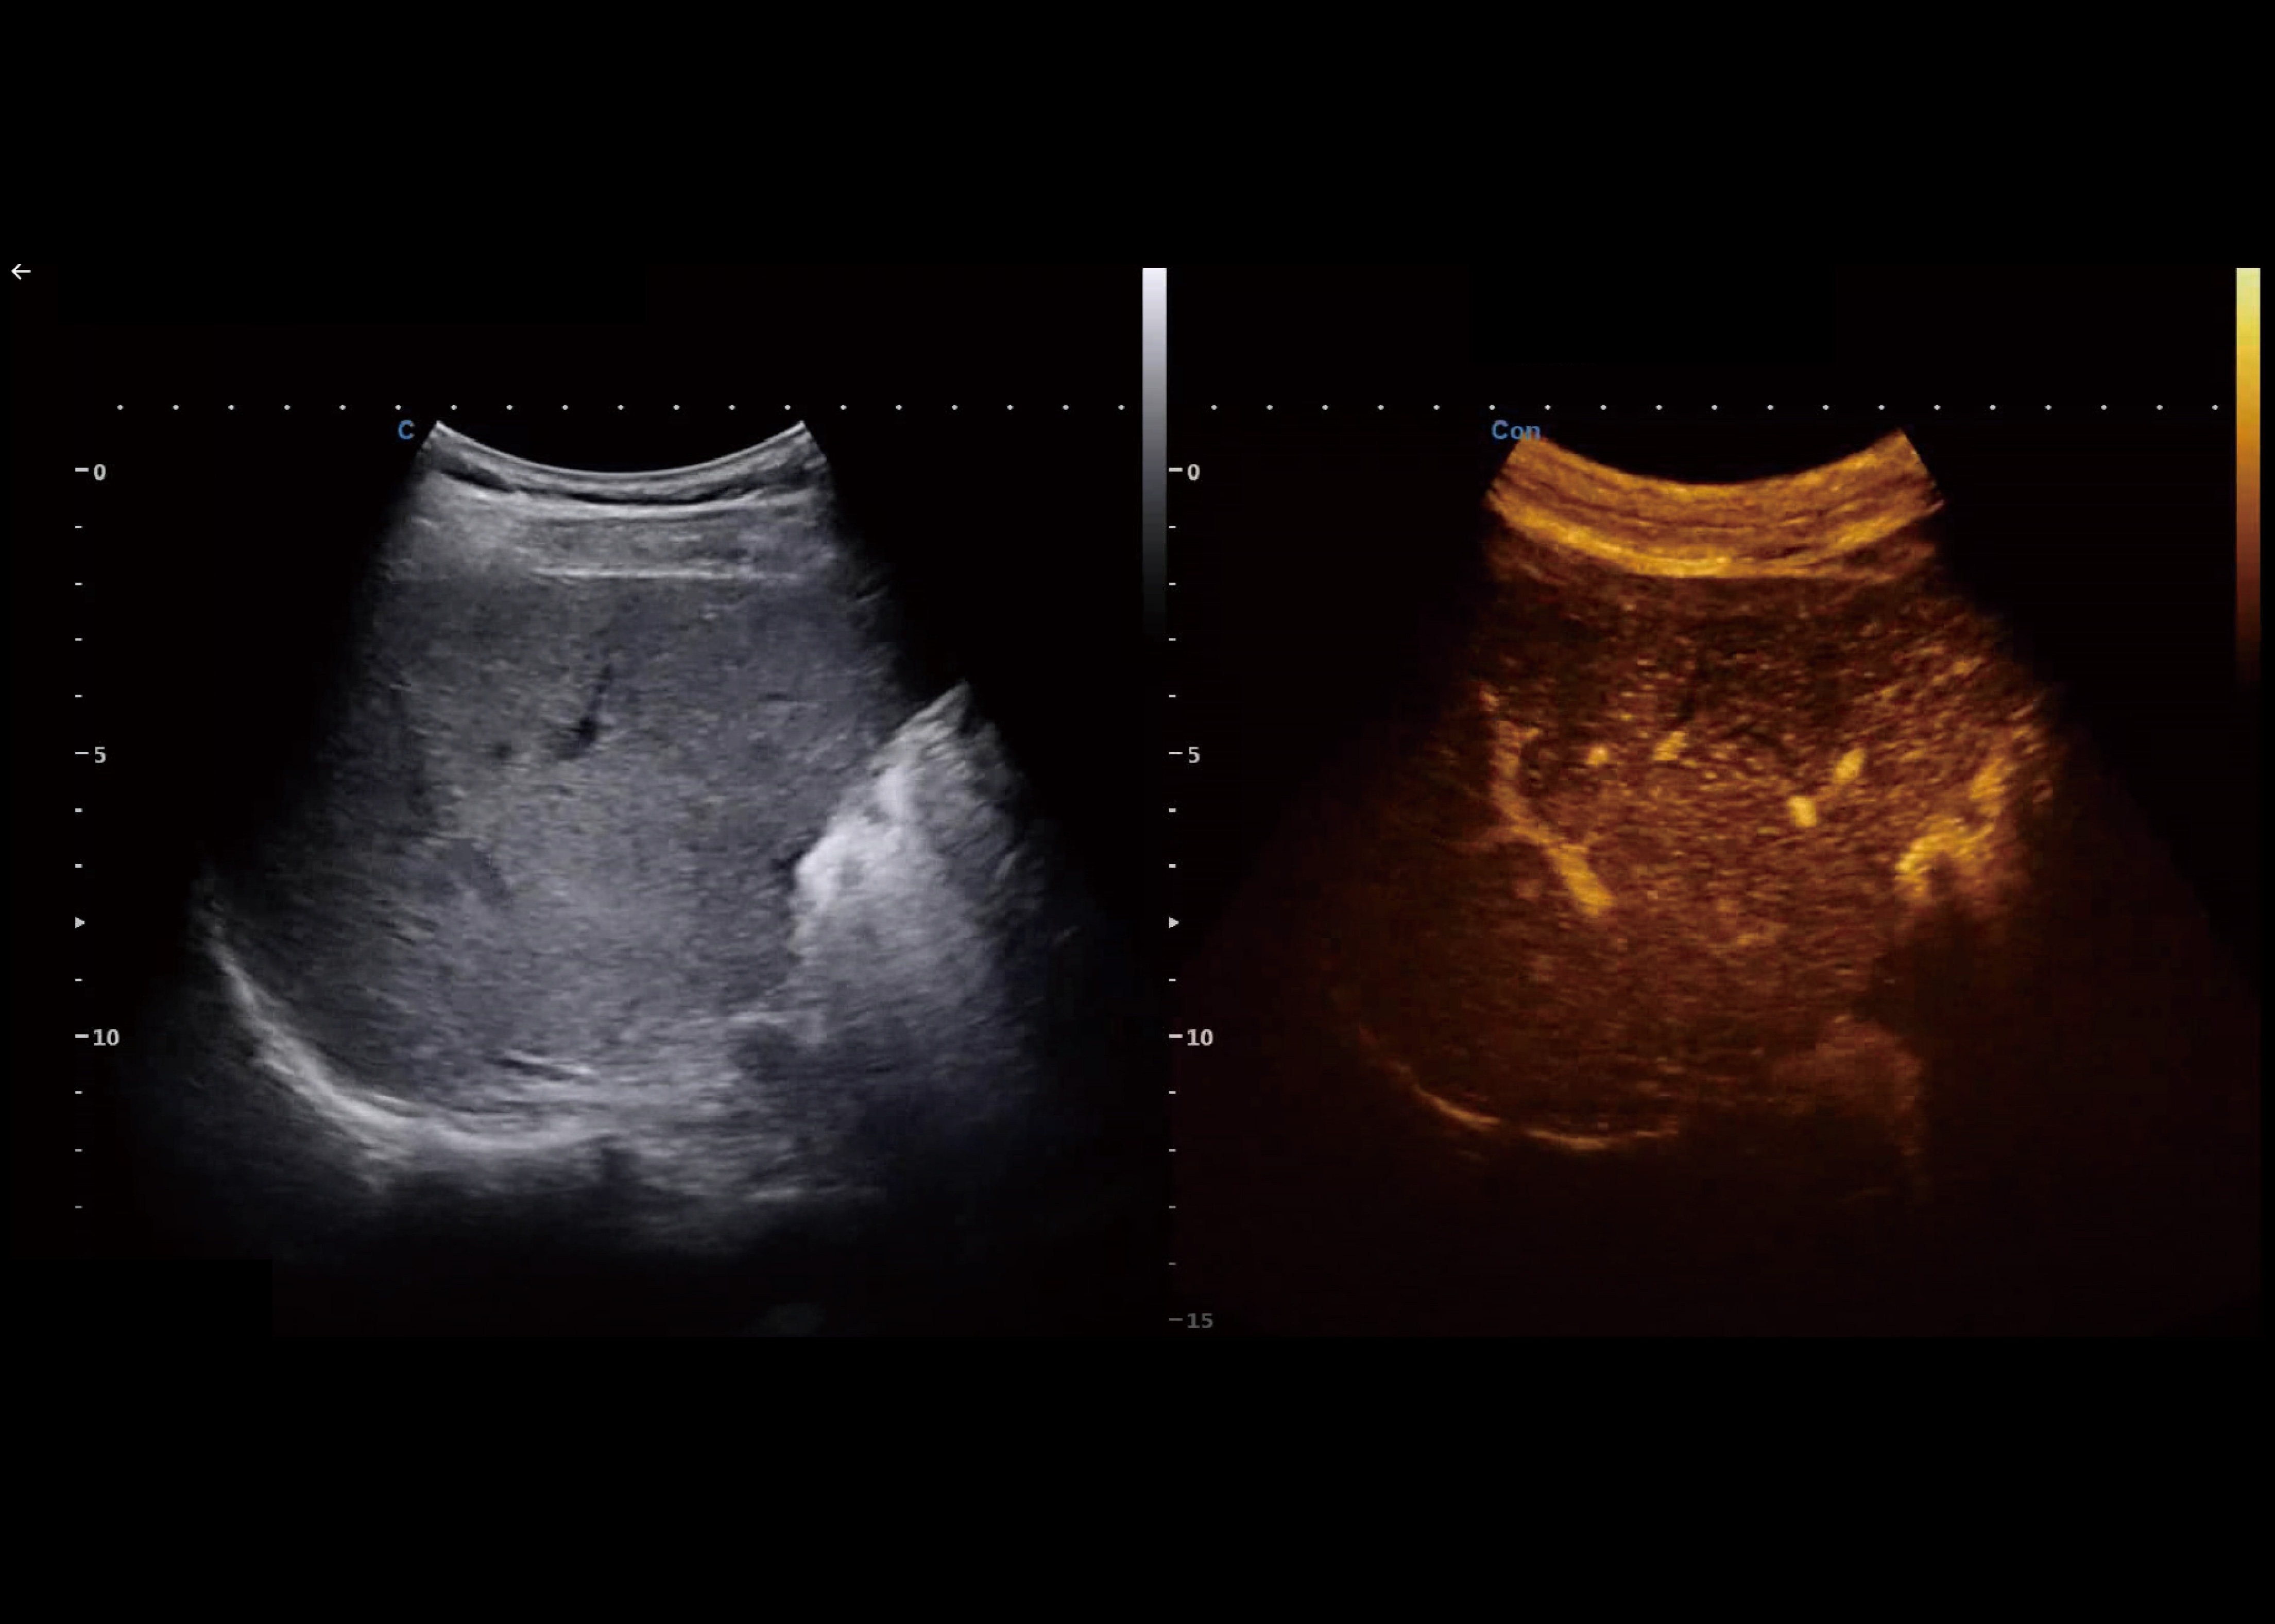

SonoContrast

● Been developed in order to visualize the micro-circulation in tissue, that is, the blood flow in imperceptible blood vessels.

● Potentially be used for improved diagnosis and therapy in several clinical situations.